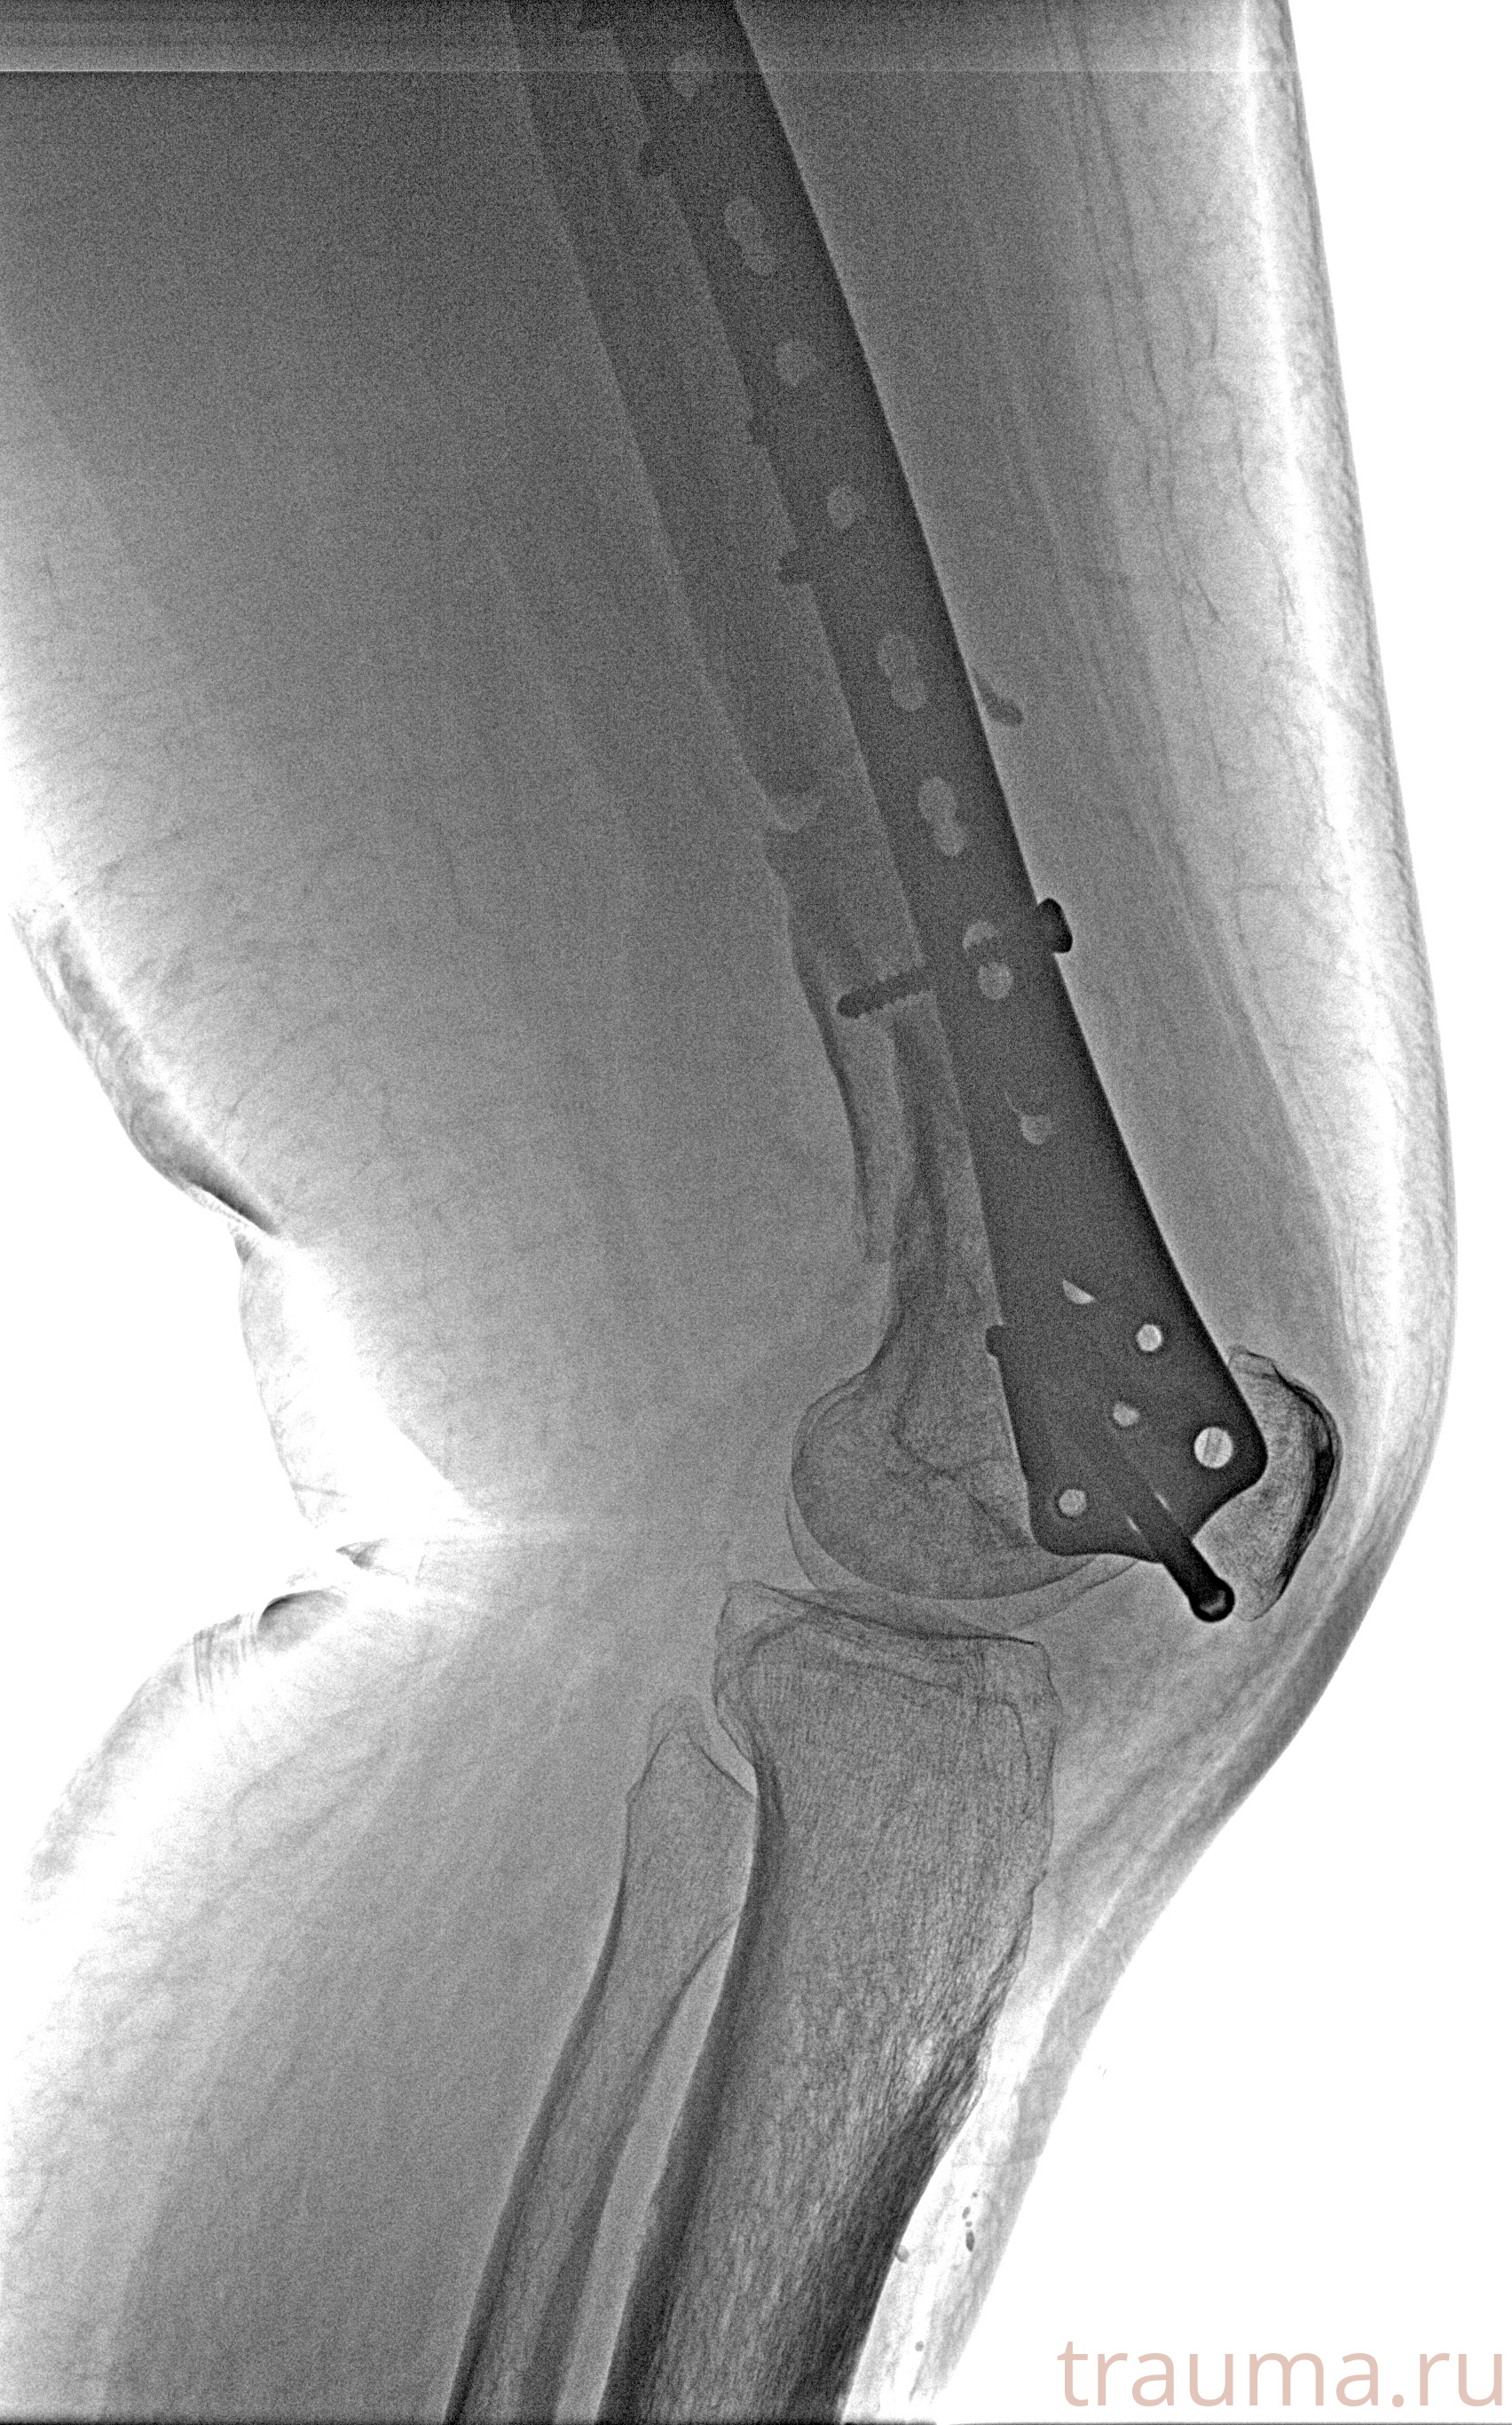

Рентгенограммы

Рентген на дому: по вашему адресу приезжает врач-рентгенолог, травматолог-ортопед с мобильным рентгеновским аппаратом, проводит диагностику травмы или заболевания, делает необходимые рентгенограммы, дает рекомендации по дальнейшему лечению. Получить качественные снимки в домашних условиях возможно благодаря уникальной методике, разработанной МосРентген Центром для института  Склифосовского